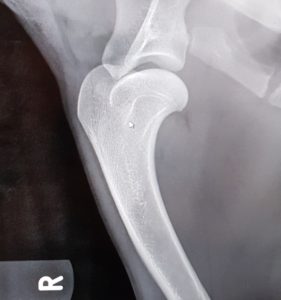

Endnu 2 hunde er blevet bedømt af DKK og fundet HD, AD og OCD frie, vi er så glade og stolte!